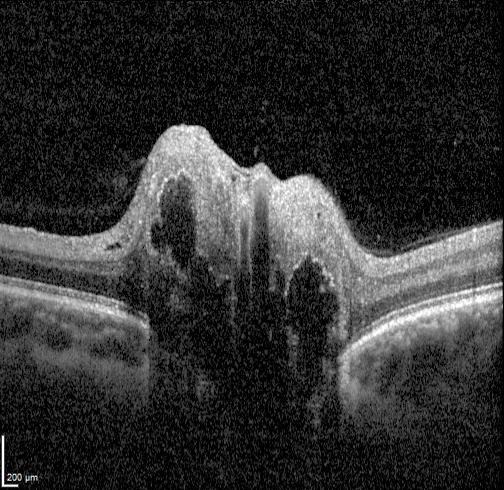

On OCT imaging, drusen appear as hyporeflective bodies with hyperreflective margins. Enhanced depth imaging (EDI) is useful to improve visualisation of buried drusen. However, in cases where the drusen is deeply buried, they may not be visible on OCT.

More infoSpectralis OCT volume and line scan (right optic disc)

More infoSpectralis OCT line scan (left optic disc)